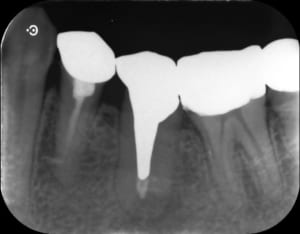

画像の通り、

かなり歯の深いところまで

長く

太い

金属の土台(メタルコア)が入ってしまっています。